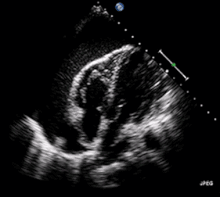

A 2D echo transthoracic echocardiogram of pericardial effusion. The "swinging" heart.

ECG: may present with sinus tachycardia, low voltage QRS as well as electrical alternans.[2] Due to the fluid accumulation around the heart, the heart is further away from the chest leads, which leads to the low voltage QRS. Electrical alternans signifies the up-and-down change of the QRS amplitude with every beat due to the heart swinging in the fluid (as displayed in the ultrasound image in the introduction) .[1] These three findings together should raise suspicion for impending hemodynamic instability associated with cardiac tamponade.

Echocardiogram (ultrasound): when pericardial effusion is suspected, echocardiography usually confirms the diagnosis and allows assessment of the size, location and signs of hemodynamic instability.[4] A transthoracic echocardiogram (TTE) is usually sufficient to evaluate pericardial effusion and it may also help distinguish pericardial effusion from pleural effusion and MI. Most pericardial effusions appear as an anechoic area (black or without an echo) between the visceral and the parietal membrane.[1] Complex or malignant effusions are more heterogeneous in appearance, meaning they may have variations in echo on ultrasound.[5] TTE can also differentiate pericardial effusion based on the size. Although it's difficult to define size classifications because they vary with institutions, most commonly they are as follows: small <10, moderate 10–20, large >20.[5] An echocardiogram is urgently needed for evaluation when there is concern for hemodynamic compromise, a rapidly developing effusion or history of recent cardiac surgery/procedures.[1]